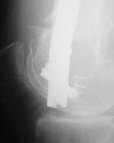

I presented a series of ~25 such cases at EuroTrauma'2004. Many cases were discussed here. I attach am example. Look also recent cases at http://www.hwbf.org/hwb/conf/alex58/scfx.htm,

THX, initial images are

1,

2.

At that moment we had in stock only the 10 mm solid nails so of course there was no idea about early weight bearing. But it was quite enough for early knee ROM excersises (see attached). Two locking screws through the distal block provided that.